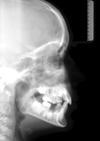

FRS

Die Fernröntgenseitenaufnahme dient der Analyse der Lage des Gebisses im Schädel. Die Auswertung wird in unserer Praxis mit Hilfe eines Computers vorgenommen.